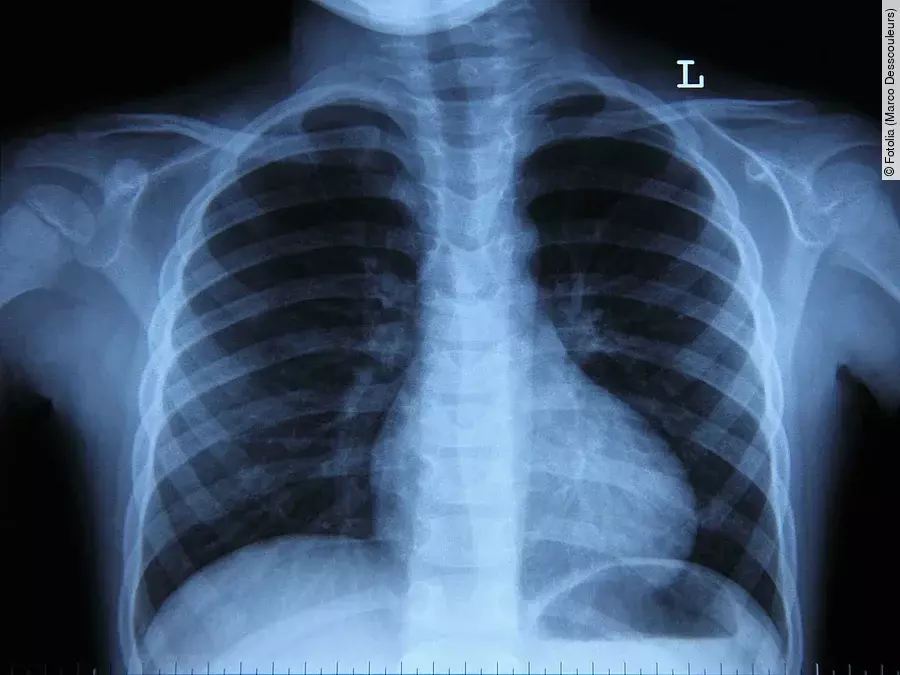

Im klinischen Alltag kommt algorithmische Bildanalyse bisher nur vereinzelt zur Anwendung. Das liegt u. a. daran, dass intelligente Bilderkennungssoftware sich nur aufwändig in den ärztlichen Workflow integrieren lässt. Zielsetzung des Forschungsprojekts ist es daher, die Voraussetzungen für einen großflächigen Einsatz dieser modernen Technologie in der radiologischen Diagnostik zu schaffen. Weltweit arbeiten Forscher daran, mit Hilfe intelligenter Algorithmen medizinische Bilder auszuwerten, um Diagnose und Therapie zu verbessern.

„Bilderkennungssoftware und Algorithmen sind viel exakter als das menschliche Auge und können auch winzigste Anomalien auf CTs oder MRTs entdecken“, erklärt Prof. Dr. Wieland Sommer, Initiator des Forschungsprojekts. Und weiter: „Durch die genauere Analyse medizinischer Aufnahmen, können nicht nur Tumore früher erkannt, sondern auch die Therapien besser angepasst werden. Unsere Vision ist es, die Vorteile intelligenter algorithmischer Bilderkennung einer Vielzahl von Patienten zugänglich zu machen. Dies erreichen wir, indem wir Bilderkennung mit strukturierter Befundung kombinieren.“